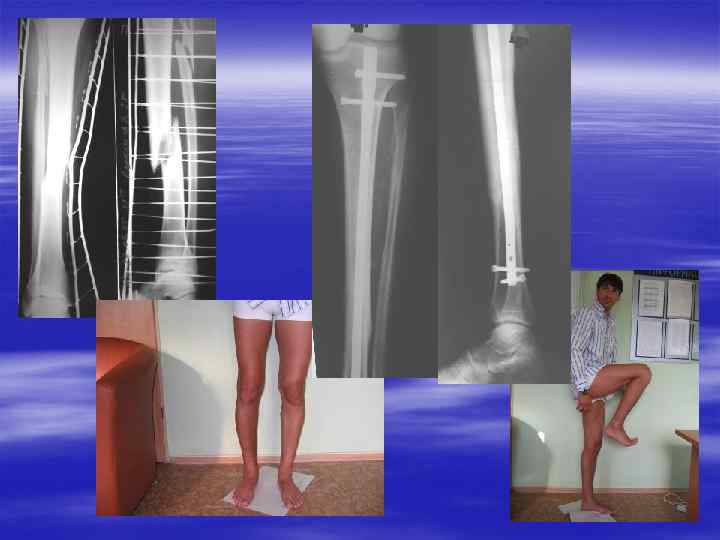

Остеосинтез переломов б/б кости типа В 2 в н/3

Отдаленный результат